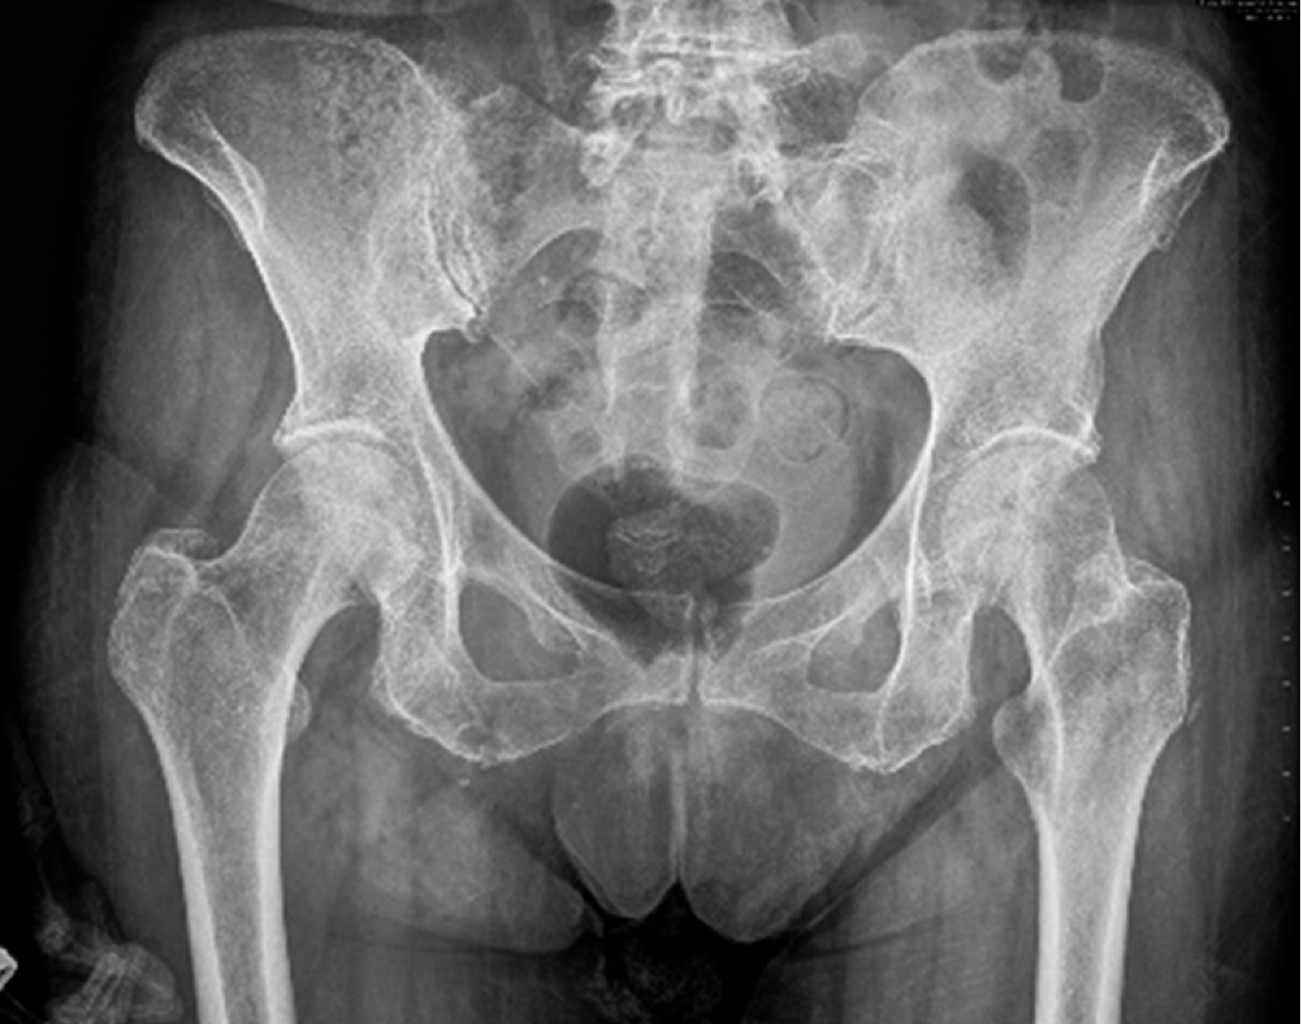

Se seleccionaron dos pacientes de 65 y 72 años. Ambas presentaron dolor en la sínfisis que les limitaba las actividades de la vida diaria. Una de ellas realizaba actividad física moderada que había tenido que cesar por completo debido a las molestias continuas. Se realizaron estudios de imagen que comenzaron con radiografías simples de pelvis (Figura 3).

Posteriormente se solicitó una tomografía computarizada (TC) de pelvis en el que se confirmaban los cambios degenerativos (Figuras 4 y 5) y una resonancia magnética que mostraba hallazgos de inflamación en las sínfisis compatibles con osteítis de pubis, asociados a edema de la musculatura adyacente. Ambas pacientes estuvieron realizando sesiones de fisioterapia y toma de antiinflamatorios no esteroideos (AINE) y corticoides con escasa mejoría. La infiltración de bupivacaina junto con corticoide fue el tratamiento más efectivo, pero pasados los dos meses la clínica, se reprodujo y se planteó en ese momento la opción quirúrgica. Las puntuaciones en la escala visual analógica (EVA) previamente a la cirugía fueron de 8 y 9, respectivamente.